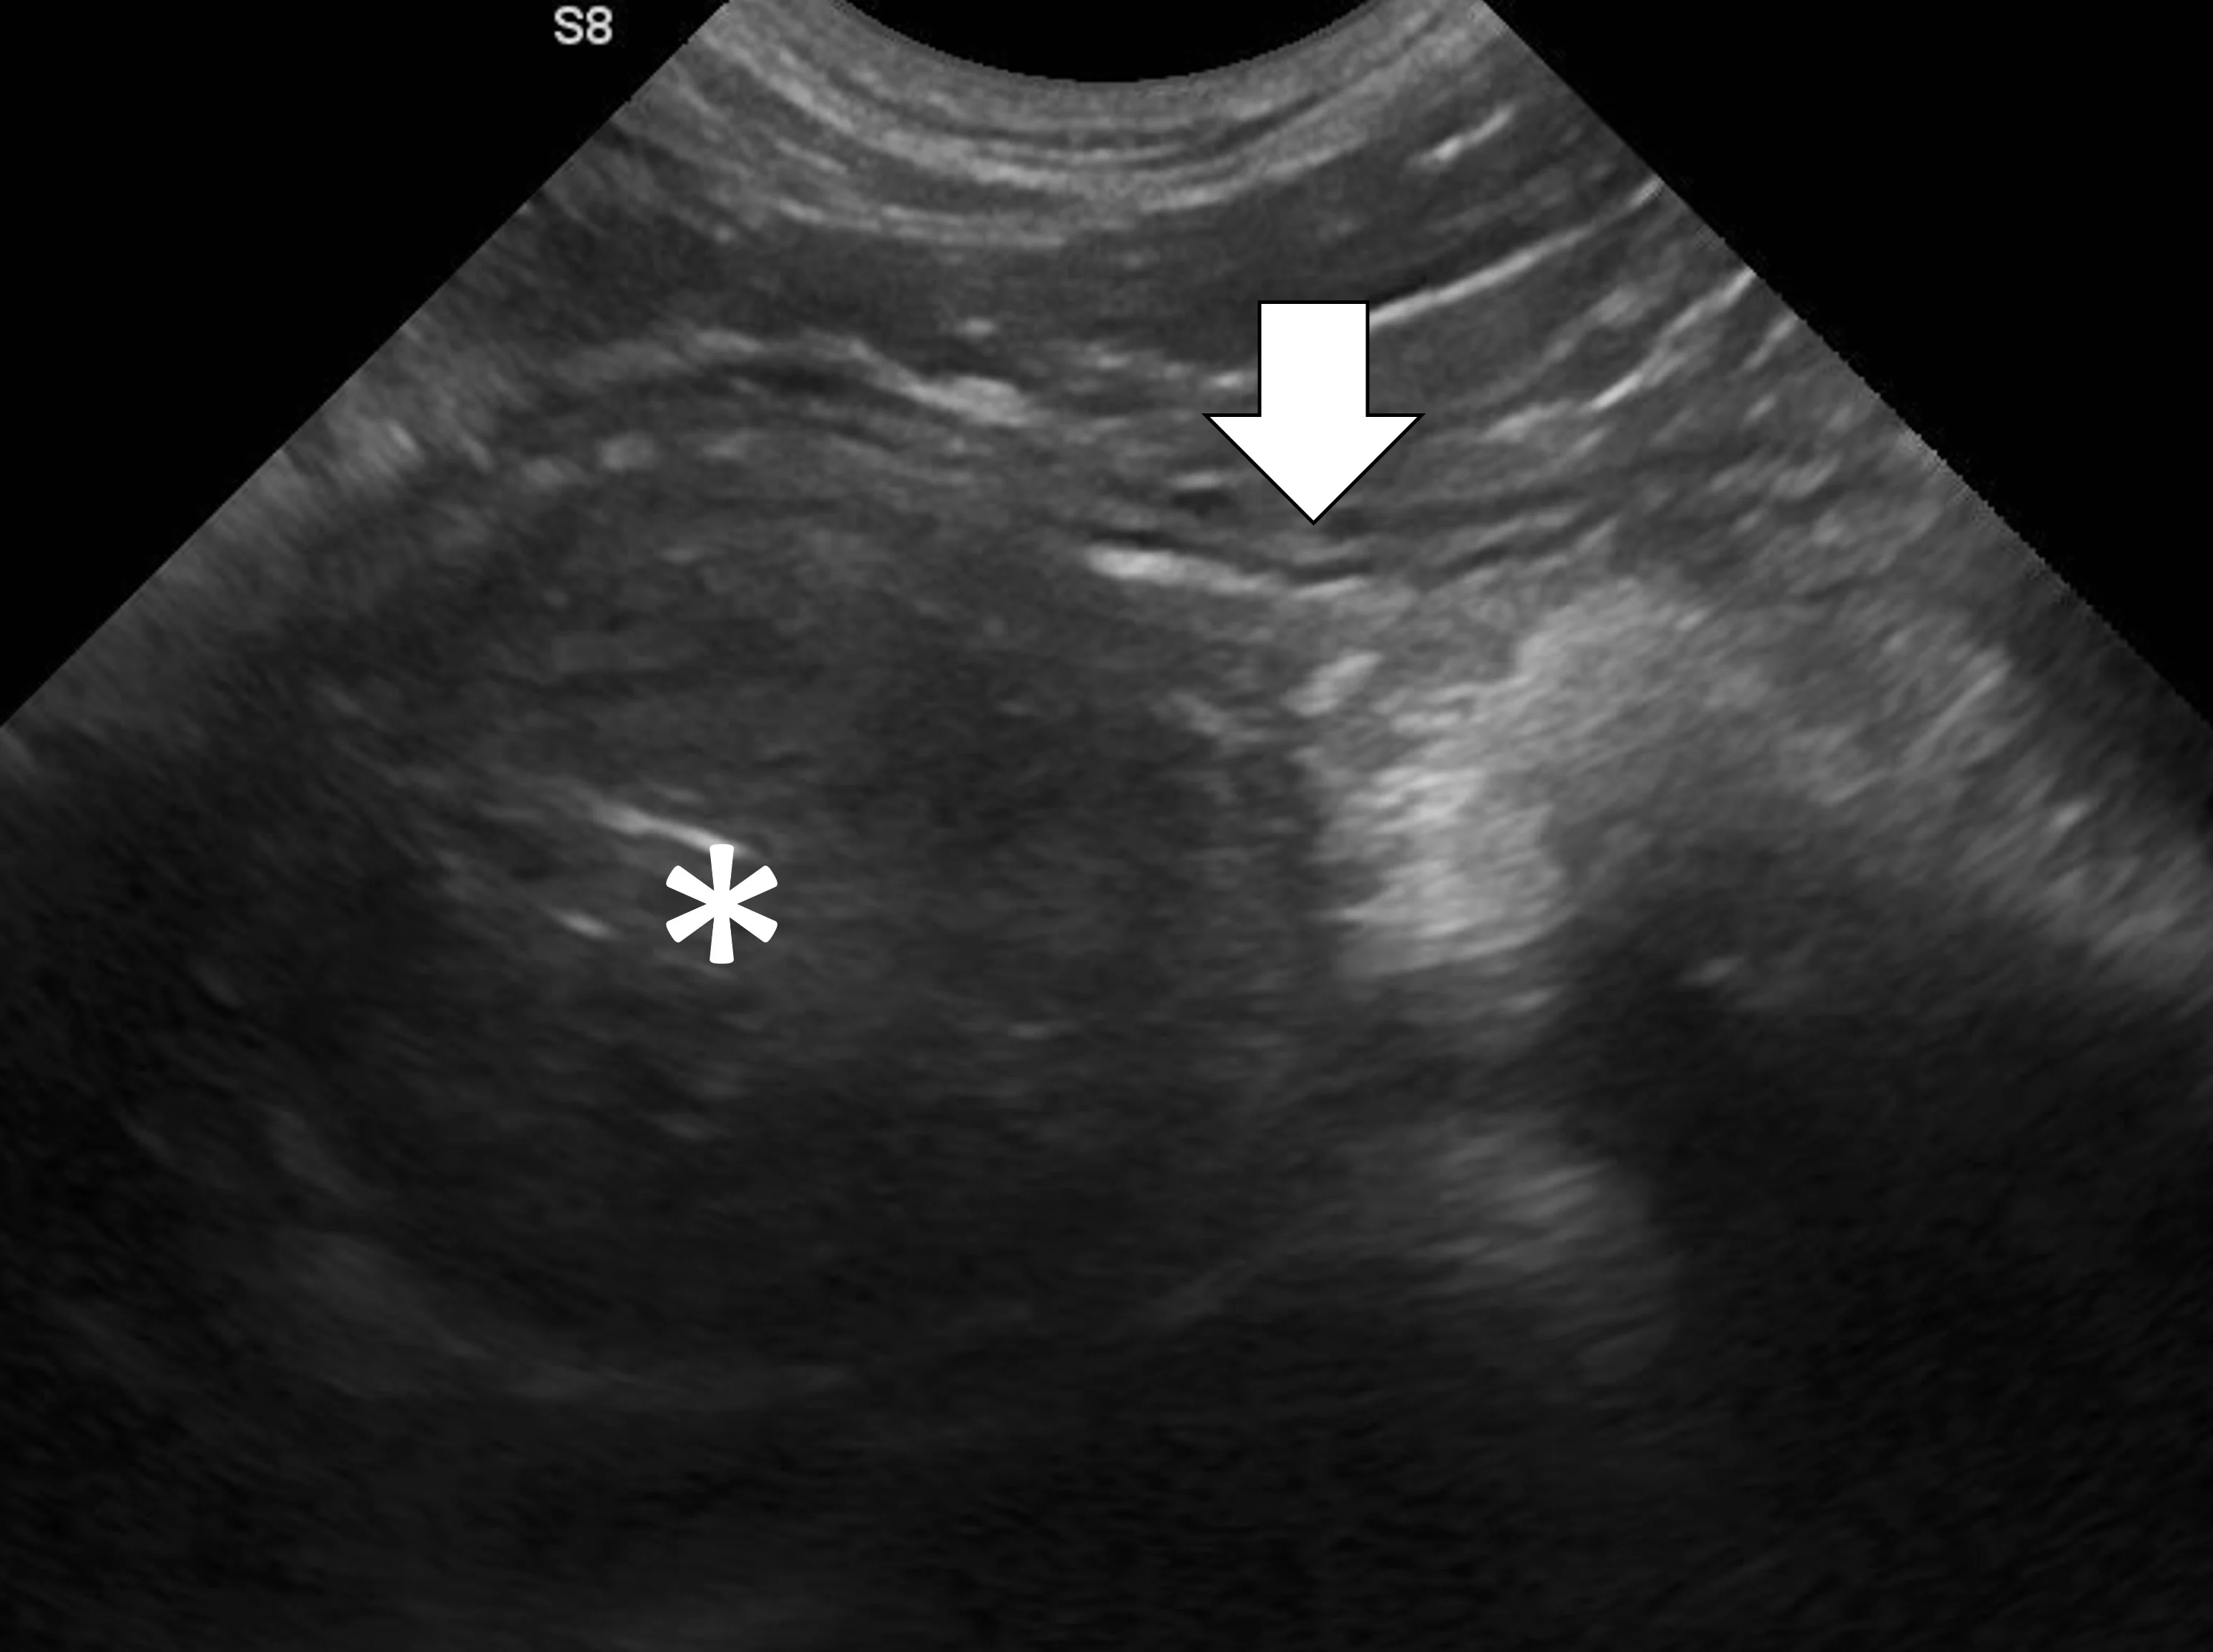

Small Intestinal Mechanical Obstructions

Small intestinal mechanical obstructions occur when a foreign body blocks the lumen of any segment of the small bowel, causing segmental dilation located orad to the foreign body (Figure 3).9-12 As the small bowel increases in size, it crowds the peritoneal cavity and begins stacking on itself with sharp, hairpin turns.9-12 Dilated portions of the small bowel usually contain a mixture of fluid and gas. One study demonstrated that a serosal-to-serosal jejunal diameter of >1.5 cm helped discern dogs with and without mechanical obstruction.1 Dilated bowel can often be followed to the site of obstruction, where it immediately normalizes aborad to the foreign body. In some patients, the foreign body may not be visualized if located deep to more superficially located gas-dilated intestines. In patients scanned in dorsal recumbency, gravity may cause heavier foreign bodies to settle deep in the abdomen. If jejunal dilation >1.5 cm is present but the site of obstruction is not initially seen, the patient may be shifted into right and then left lateral recumbency and the midabdomen reinterrogated. In addition, one study suggested that a foreign body may be palpated in a majority of cases13; physical examination may therefore expedite ultrasonography. If the foreign body can be manually held or trapped against the body wall, ultrasonography can be performed on that location; however, identifying the site of obstruction is not always necessary if segmental dilation is present and the clinical picture supports a diagnosis of mechanical obstruction.

Abdominal ultrasound of a 9-month-old spayed Australian cattle dog with a surgically confirmed small intestinal mechanical obstruction. There is moderate small intestinal dilation (asterisk) with hyperechoic fluid, ingesta, and gas measuring 2.1 cm in diameter at the level of the white calipers oral to a pecan foreign body (pound sign) that is visible as a hyperechoic surface with distal acoustic shadowing. The small intestine is normal and not dilated immediately aboral to the foreign body (arrow), with a small volume of intraluminal gas causing reverberation artifact.